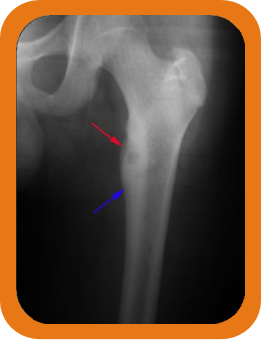

- Bone Fractures: Evaluation of fractures or bone density problems.